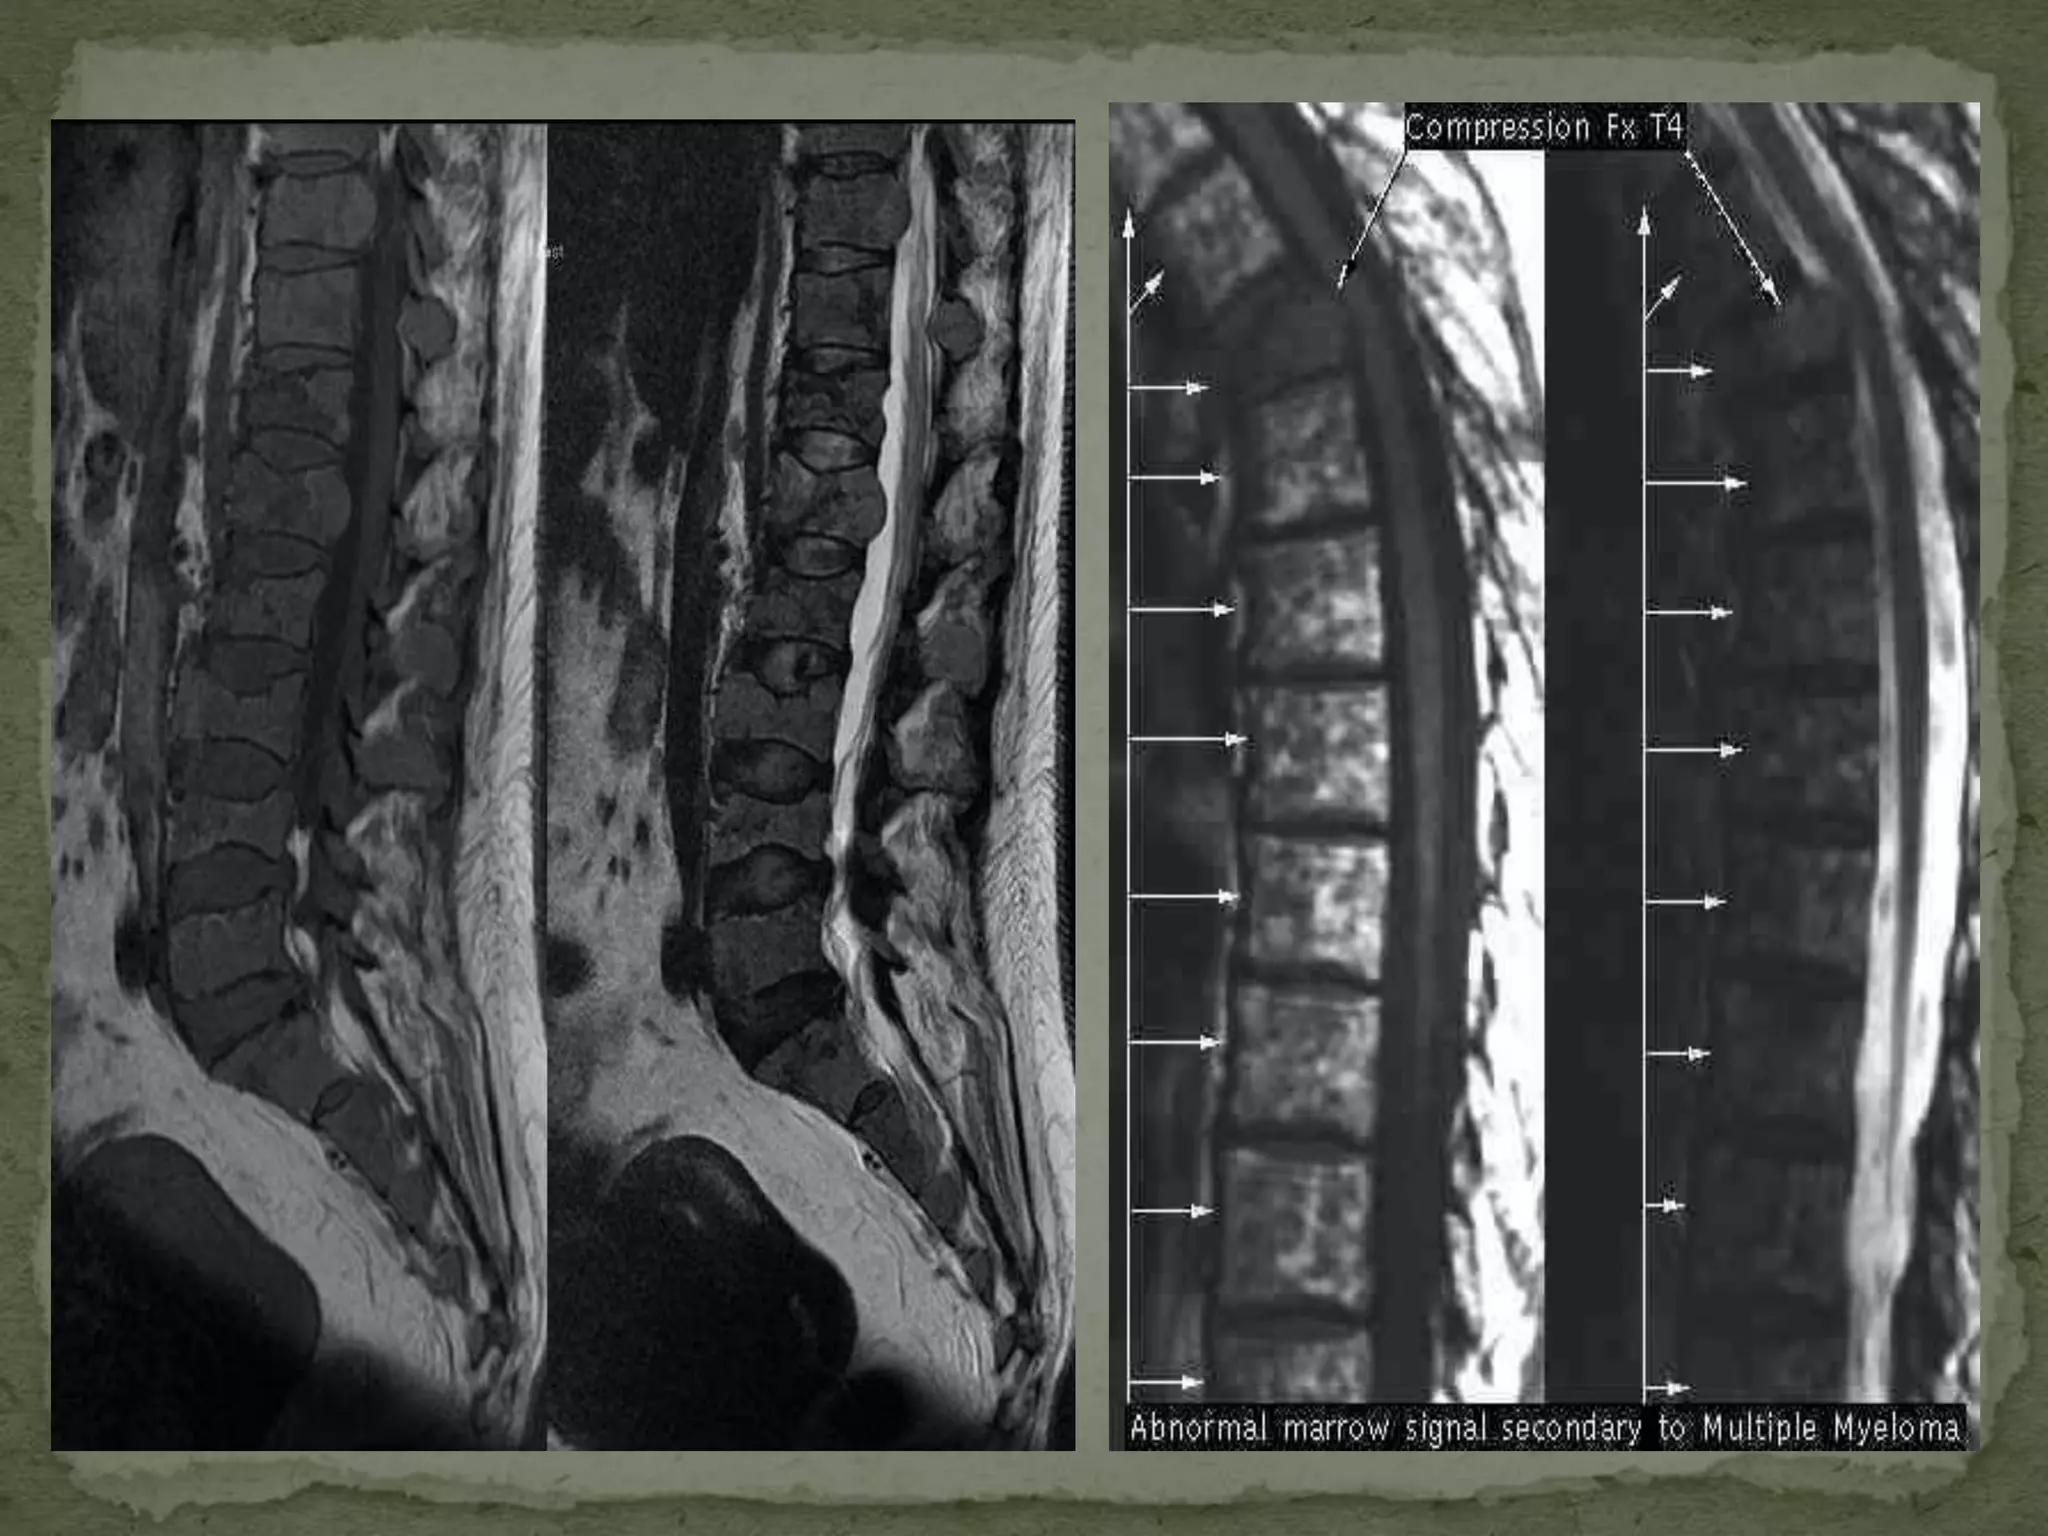

 It is a Malignancy characterized by monoclonal

proliferation of malignant plasma cells.

 Nearly always systemic.

 MM is most common primary neoplasm of spine with

the majority occurring in the thoracic and lumbar

spine.

 Most patients are men, 60 years of age or Older.

 Fatal within 4 years of diagnosis.

 Single vertebrae may be involved i.e. plasmacytoma

 Diagnosis confirmed by

1. At least 10% abnormal plasma cell

2. Lytic bone lesion

3. Monoclonal gammopathy ( Protein electrophoresis,

urinary Ben Zones protein)

4. Anaemia, High rise of ESR

 M R I show Progressive metastatic disease to thespine

 Recommended forinvestigating the suspected lesions in terms of-  Level  Extent  Bone marrow infiltration  Infiltration to muscles, vessels  Infiltration to nerve roots, spinal cord & thecal sac

• 35.

 M RI show Progressive metastatic disease to thespine